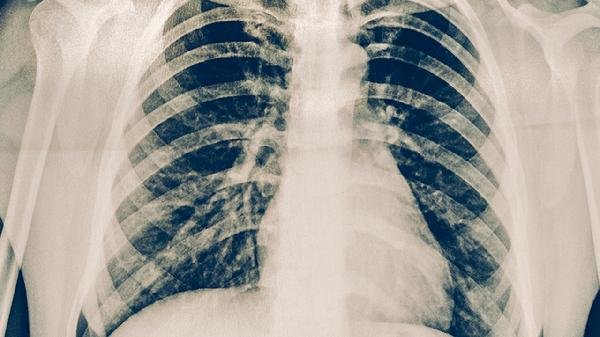

胸部X线检查通过影像学手段观察肺部病变特征,适用于筛查和辅助诊断。典型表现包括上肺野浸润影、空洞形成等,但需结合其他检查确诊。该检查属于无创物理诊断,不存在传染可能性。对于疑似病例,即使X线显示异常也需进一步进行病原学检测。